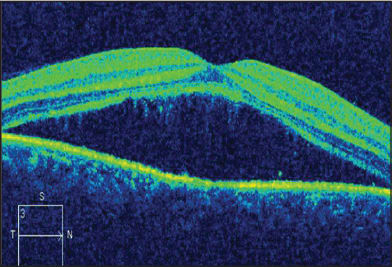

Figure 2 ( SD-OCT image of the above patient, showing neurosensory detachment.

Central serous chorioretinopathy is characterized by the development of neurosensory detachment of the macula with or without concurrent retinal pigment epithelial detachments and serofibrinous subretinal exudation.